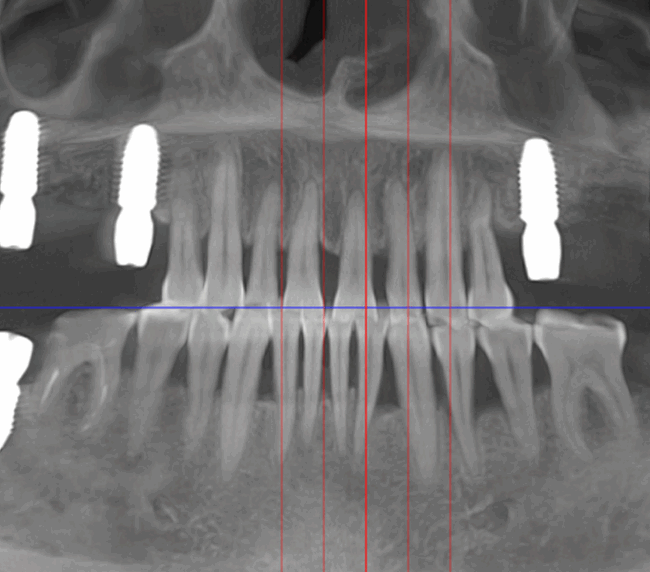

- Consultație, radiografie și plan de tratament personalizat

- Tehnologie CAD/CAM și scanare digitală 3D